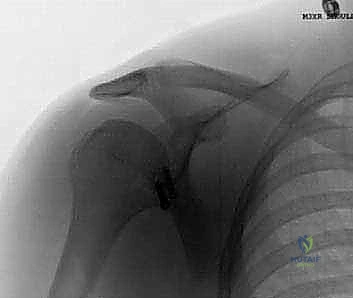

- التصوير بالأشعة السينية (X-rays): لاستبعاد وجود كسور عظمية مصاحبة للخلع، مثل كسر هيل-ساكس (Hill-Sachs Lesion) وهو انبعاج في رأس عظم العضد.

- التصوير بالرنين المغناطيسي (MRI / MR Arthrogram): المعيار الذهبي لتشخيص الأنسجة الرخوة. يوضح هذا التصوير بدقة متناهية حجم تمزق الشفا الحقاني (آفة بانكارت)، حالة الأربطة، ودرجة ترهل محفظة المفصل.